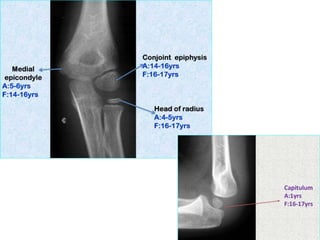

Elbow joint

• Secondary ossification Centres : (3 bones; 6 Ocs)

Capitulum (C) - appearance - 1 year of life

Head of Radius (R)– appearance -4 to 5 years

Medial Epicondyle (ME)

Appearance – 5 to 6 years

Fusion – 16 to 17 years

Trochlea (T) – appearance – 9 to 11 years

Olecranon Process of Ulna (OP)

Appearance - 8 to 9 years

Fusion- 16-17 years

Lateral Epicondyle(LE) – 11 to 12 years

Conjoint (Composite)Epiphysis (CE) [fusion of C+T+LE]

Formation – 14 to 16 years

Fusion – 16-17 years

Note: Fusion of O.Centres at elbow joint is 16-17 years in male, 15-16 years in female